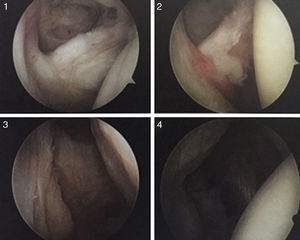

En este consenso puede observarse la evaluación de la patología del manguito de los rotadores con la estrategia PEARL, donde la P es el patrón de la lesión si es parcial articular, bursal o intersticial, y si son de espesor completo según la clasificación de Burkhart. En cuanto a la E, significa extensión, donde se toma la clasificación de Cofield (denominada con la letra C) de 1 a 4, de acuerdo con el hallazgo intraoperatorio. En cuanto al compromiso de la lesión del subescapular, se describen las lesiones según la clasificación de Lafosse que utiliza la numeración de 1 a 5 para determinar la extensión de la lesión (figs. 12 y 13):

- 1.

Muestra una deslaminación del tendón en el borde superior.

- 2.

Desgarro parcial en el tercio superior del tendón.

- 3.

Desgarro superior completo con inserción muscular inferior preservada.

- 4.

Desinserción completa del subescapular sin signos de artropatía.

- 5.

Rotura masiva con signos de artropatía.